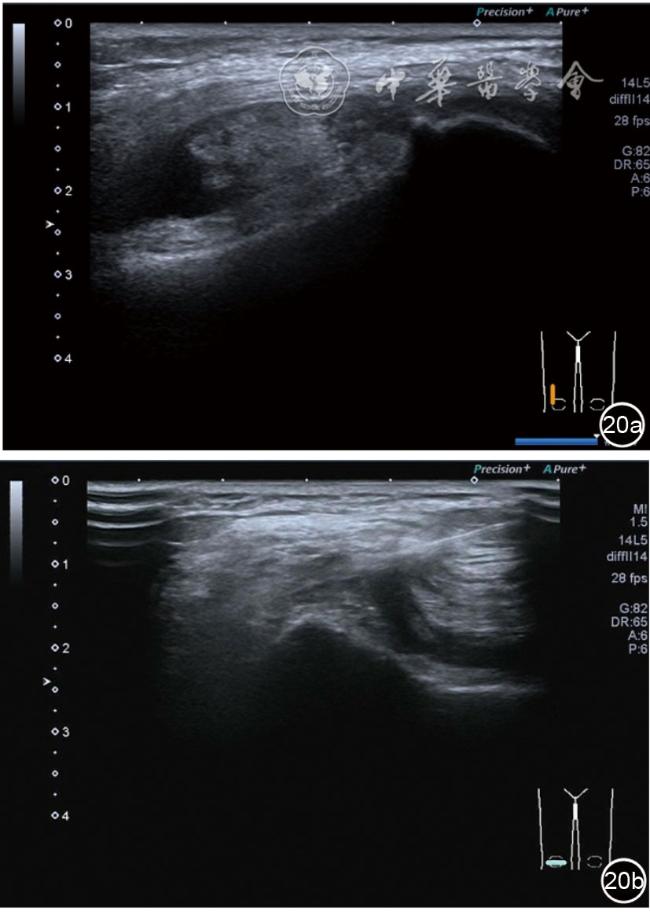

3.膝关节内局部治疗。随着病情发展,静态结构失衡,膝关节内部结构发生变化,会出现软骨损伤、脱落,关节间隙变窄,内外间隙不等,骨赘形成等。膝关节内局部治疗包括关节内症状性骨赘剥离、玻璃酸钠及PRP注射等。(1)膝关节内症状性骨赘针刀剥离松解治疗。由于软骨缺损或者力平衡失调,在关节内脱落软骨区会出现骨赘。部分骨赘引起疼痛,或者与髌骨撞击出现临床症状需要治疗。针刀剥离目的不是去除骨赘,而是剥离松解,缓解或者消除疼痛。以股骨外髁骨赘为例。患者平卧位,膝关节屈曲100°~120°。一般选用10 MHz超声探头,穿刺区域常规消毒,探头涂抹耦合剂后套入无菌手套碘伏消毒或使用无菌耦合剂。将探头置于患者皮肤表面,短轴扫查,显示关节面与骨赘,选用25G注射针,抽吸1%利多卡因3 ml于骨赘周围进行分层麻醉。选用直径1 mm的Ⅰ型2号针刀,在超声引导下从外侧向内侧到达骨赘,反复剥离,一般5~8刀后拔出针刀结束治疗(图18),局部压迫5分钟,无菌敷料覆盖。(2)膝关节髌上囊积液治疗。髌上囊积液在膝关节骨关节炎比较常见,尽管积液量可能很大,但通过软组织松解治疗后,大部分患者积液会减少或者消失。所以积液的治疗可以放在后面处理。超声引导下抽出积液,药物注射是常用的治疗方法。膝关节炎积液的治疗通常包括关节内皮质类固醇激素或者臭氧注射。如果慢性以滑膜丛型增生为主,针刀有限切割增生滑膜加药物注射可提高疗效。①髌上囊积液抽吸加臭氧注射治疗。患者平卧位,膝关节屈曲30°~60°,膝下垫一软枕。选用10 MHz超声探头,治疗前消毒准备同骨赘针刀剥离松解治疗。将探头置于患者皮肤表面,短轴扫查,找到积液最多处,应用22G针头,直接穿刺进入髌上囊抽出液体,然后根据髌上囊大小制备35 μg/L的15~20 ml臭氧注入髌上囊内拔出针头(图19),局部压迫2分钟,无菌敷料覆盖。②髌上囊慢性滑膜炎针刀切割松解治疗。患者平卧位,膝关节屈曲30°~60°,膝下垫一软枕。选用10 MHz超声探头,治疗前消毒准备同骨赘针刀剥离松解治疗。将探头置于患者皮肤表面,长轴或短轴扫查,找到积液最多处,用一次性5 ml注射器抽吸1%利多卡因3 ml于髌上囊进行分层注射麻醉,囊内也要注射适量麻药,尽量抽出积液。选用直径1 mm的Ⅰ型2号针刀,长轴扫查从近端向远端,短轴扫查从外侧向内侧,在超声引导下进入囊肿内对内壁及增生滑膜的不同方向、角度进行反复切割(图20),一般2~3分钟拔出针刀,然后囊内注射1%利多卡因3 ml+曲安奈德15 mg,结束治疗,局部压迫5分钟,无菌敷料覆盖。(3)膝关节腔PRP注射治疗。关节腔注射主要是为了修复软骨,如果不是为了治疗积液,不主张应用激素类药物。目前主要的注射药物为玻璃酸钠、PRP。按照传统的注射部位,多为髌上内、外或者髌下内、外注射点,但是超声不能观察到注射针的位置,药物也不能很好到达软骨损伤的部位,效果受到影响(图21)。膝关节软骨损伤的主要部位在髌股关节的股骨髁,超声可以很好地显示这一部位,并能显示软骨变薄。因此,由这个路径平面内进针注射,可以很好显示穿刺针的路径与位置。以注射PRP为例。患者平卧位,膝关节屈曲100°~120°,选用10 MHz超声探头,治疗前消毒准备同骨赘针刀剥离松解治疗。将探头置于患者皮肤表面,短轴扫查显示关节面,应用25G注射针头,抽吸1%利多卡因2 ml由内侧进针进行分层麻醉直达关节软骨面。制备4.5 ml PRP,直接注射到关节面,液体顺关节面分布,注射完毕拔出针头(图22)。局部压迫2分钟,无菌敷料覆盖。(4)髌骨软化超声影像融合技术下PRP注射治疗。髌骨软化是指髌骨关节面的软骨损伤,软骨下骨囊变,MRI能够明确诊断,但是超声不能显示。应用超声与MRI的影像融合技术,依据MRI明确注射部位,在超声引导下可将药物精准注射到软骨损伤的部位。患者平卧位,膝关节屈曲30°,下面垫一软枕。一般选用10 MHz超声探头,治疗前消毒准备同骨赘针刀剥离松解治疗。将MRI的原始图像数据导入超声设备中,进行手动影像融合,完全融合后,确定穿刺靶点,以MRI图像为目标,以超声图像为实时引导进行穿刺,到达目标后,注射提前制取的PRP 3 ml(图23),注射完毕拔出针头,局部压迫3分钟,创可贴覆盖。

图20 超声引导下髌上囊慢性滑膜炎针刀切割松解治疗